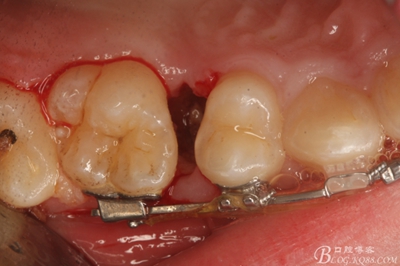

圖11.仔細(xì)考慮之后,在14頰側(cè)做垂直切口,切口長度僅達(dá)膜齦聯(lián)合處,做小切口。

圖12. 做垂直切口+齦溝內(nèi)切口,形成角形瓣,暴露出15根面。

圖13. 用小球鉆去除約1mm牙槽骨,暴露15牙根面約5mm。